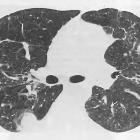

Round

atelectasis in sarcoidosis. Chest CT revealed a round pleural-based mass at the level of the right lower lobe with the characteristic comet tail sign of curving of vessels into the lesion with peribronchovascular and subpleural nodules.